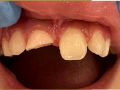

Bezpośrednia licówka kompozytowa w odcinku przednim wykonana…